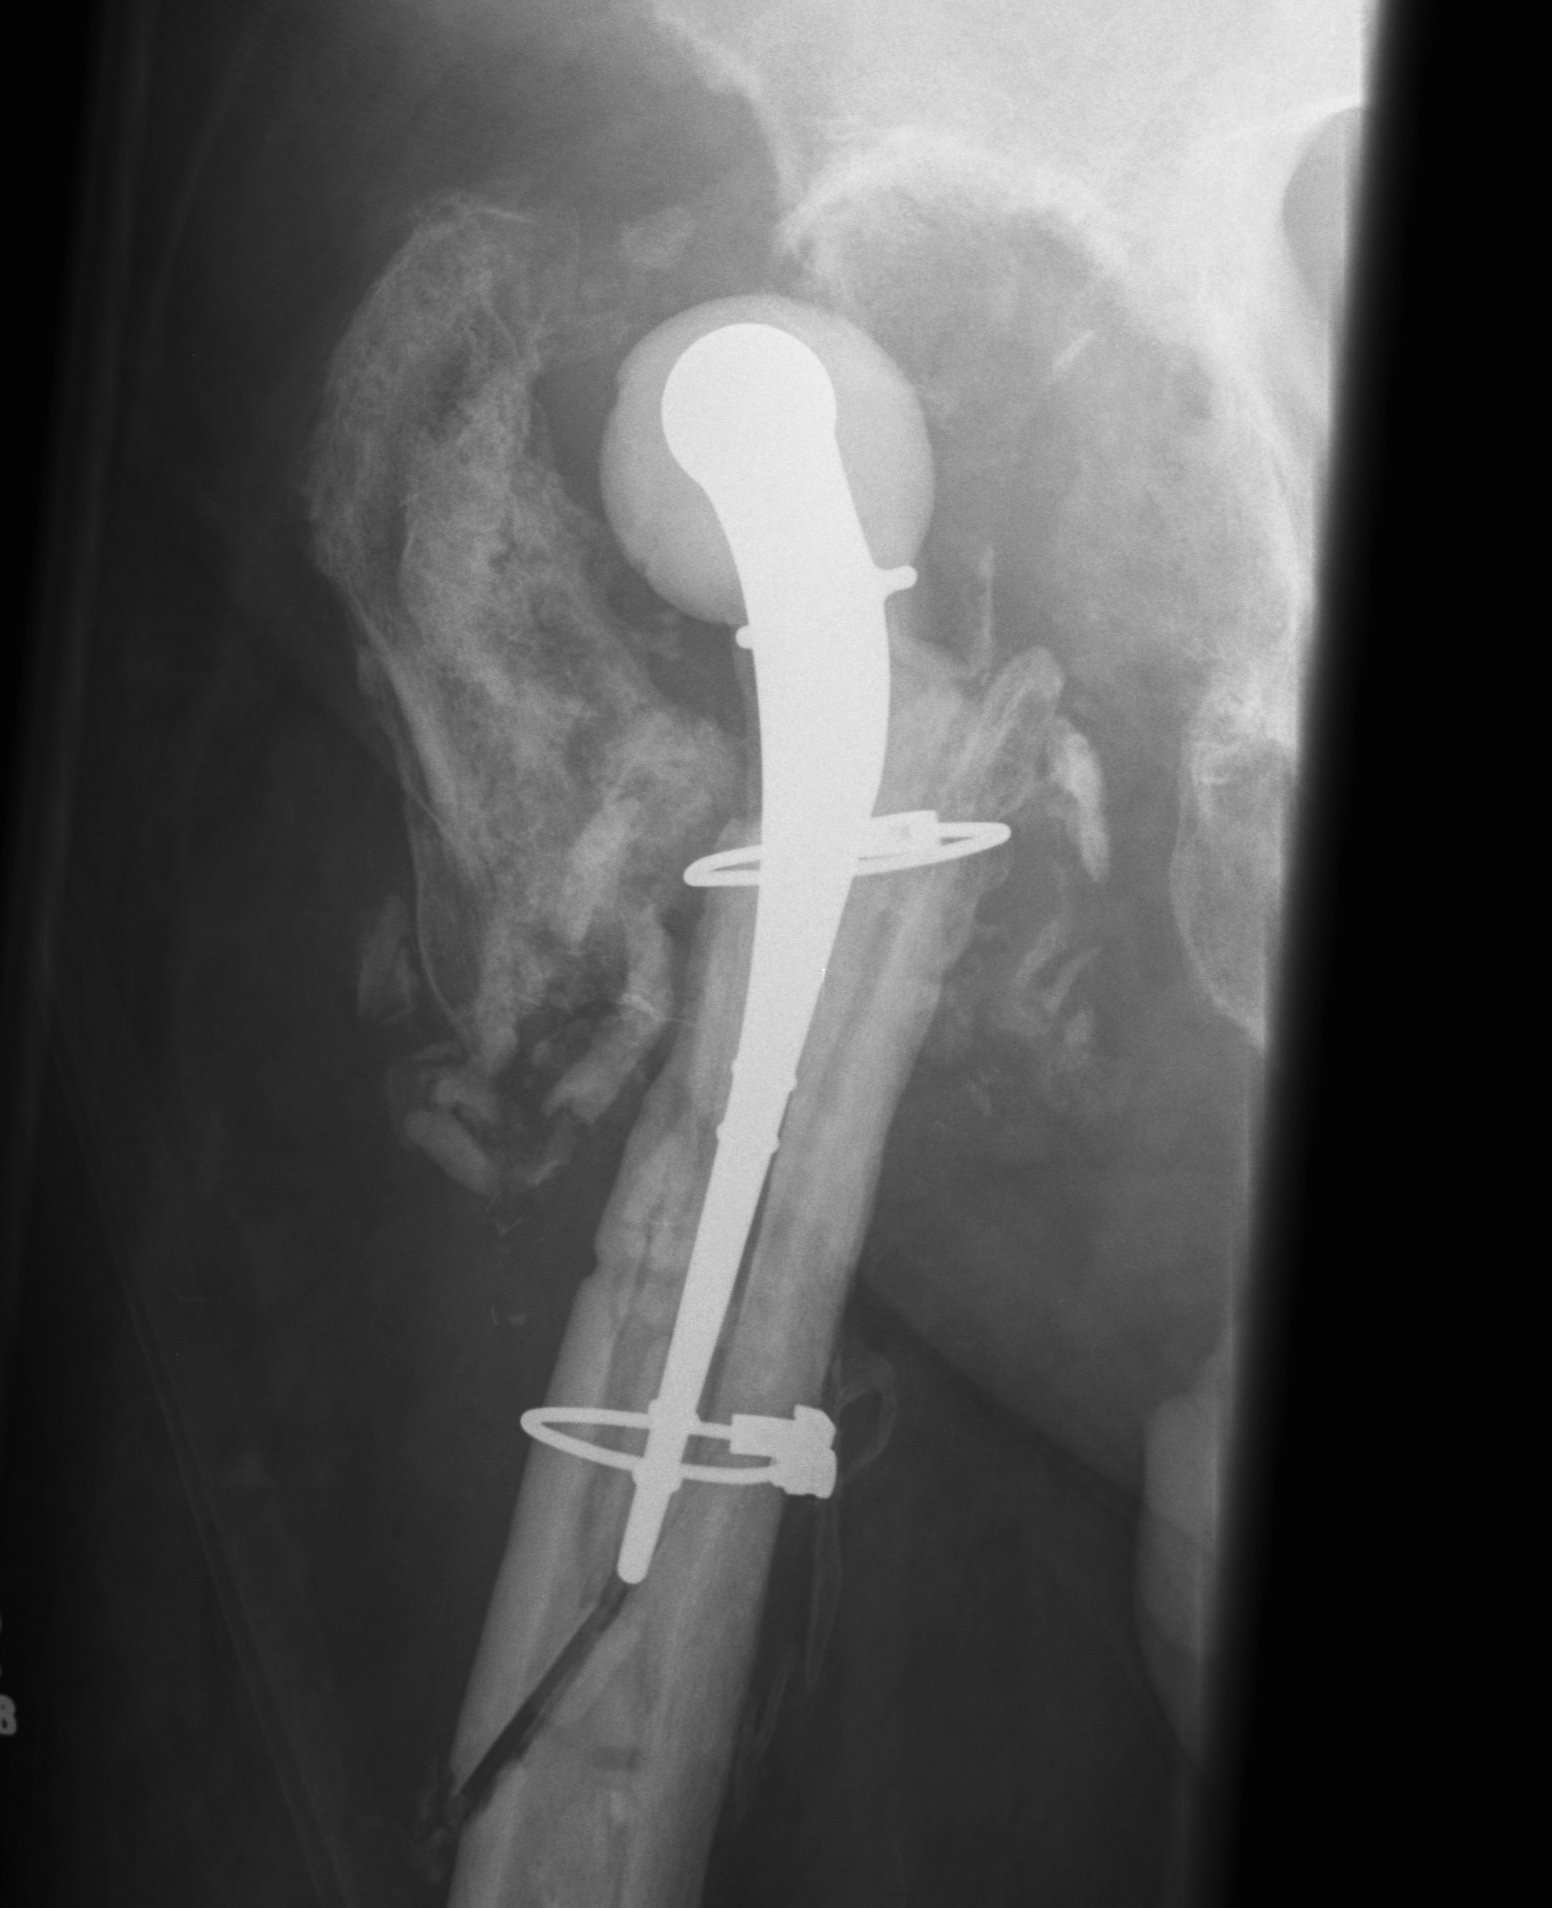

Two-Stage Revision

Technique

First stage

- debridement + removal of implants and all cement

- insert antibiotic impregnated cement spacer

Types of spacers

- hand made +/- metal reinforcement

- moulds +/- metal reinforcement

- prefabricated

- antibiotic-coated prosthesis

Complications

Dislocation / bone loss / prosthesis fracture / femur fracture

Jones et al J Arthroplasty 2019

- 185 antibiotic cement spacers

- 53% molds / 30% antibiotic coated prosthesis / 12% handmade / 4% prefabricated

- 9% dislocation

- 8% spacer fracture

- 7% periprosthetic fracture